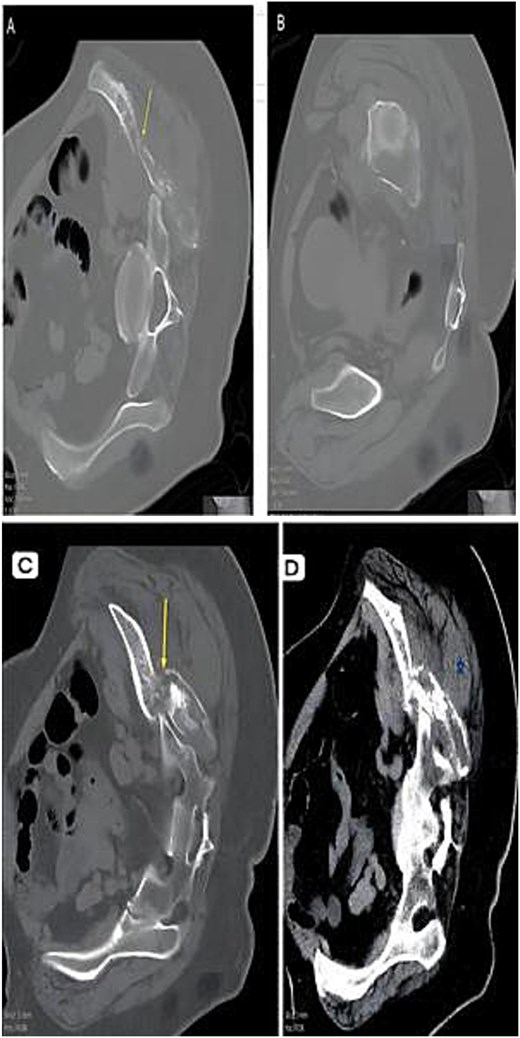

A 51-year-old woman presented in 2014 with headache and progressive right-sided weakness. MRI showed a lobulated right parietal extra-axial mass (7 × 5 × 5 cm) with homogeneous enhancement, vasogenic oedema, and midline shift. She underwent complete surgical resection followed by adjuvant radiotherapy. Histopathology demonstrated spindle-cell and meningothelial proliferation arranged in whorls with necrosis and a mitotic count of 6/10 HPF (Fig. 1). IHC was positive for EMA and vimentin but negative for cytokeratin, consistent with atypical meningioma (WHO Grade II). Ten years later, she developed progressive left-hip pain. Computed tomography (CT) of the pelvis revealed a lytic destructive lesion involving the left iliac bone with soft-tissue extension (Fig. 2). CT-guided biopsy showed tumor cells morphologically identical to the original specimen. IHC was positive for EMA and PR and negative for S-100, confirming metastatic meningioma (Fig. 3). Systemic imaging showed no visceral metastases.

CT composite. (A) Axial CT—Lytic destructive lesion with cortical breach. (B) Follow-up CT—Progressive osseous destruction & soft-tissue expansion. (C) Bone window—Cortical destruction (arrow). (D) Contrast CT—Enhancing soft-tissue mass replacing marrow (asterisk).